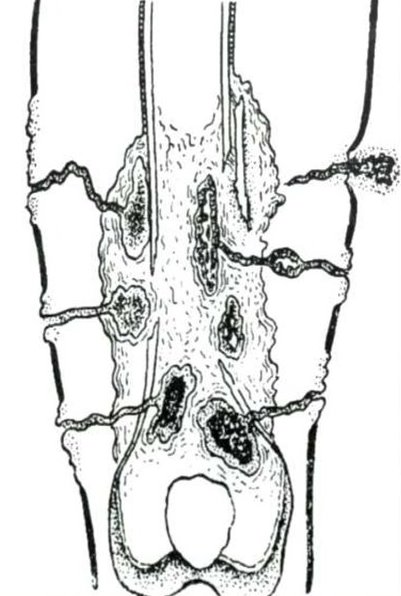

Рентгеновские снимки посттравматического остеомиелита челюсти: Медицинские случаи

Раздел: Образы вокруг